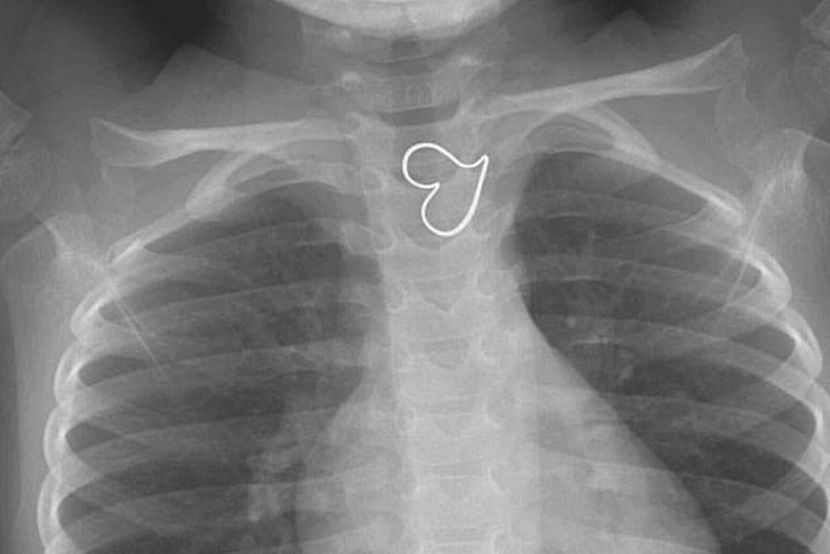

Imbasan X Ray Tunjukkan Ada Hati Di Dada Budak Usia 3 Tahun Dunia Mstar